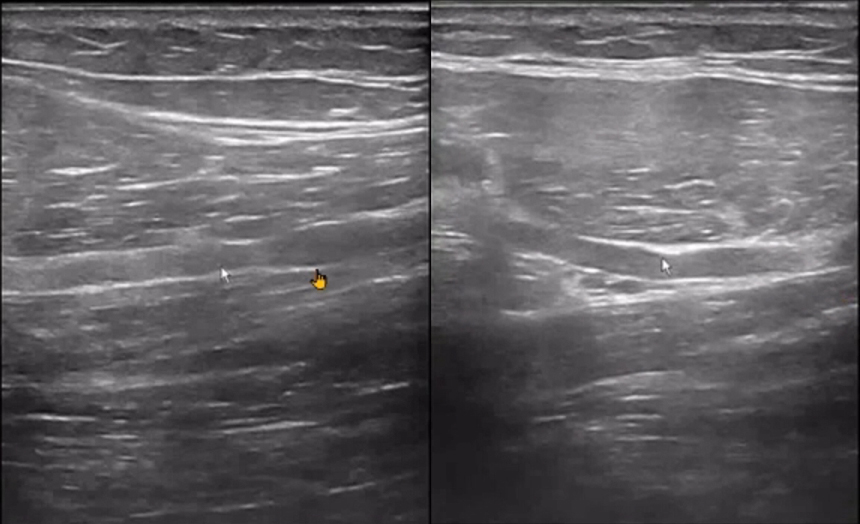

The patient experienced significant pain during wrist extension, indicative of "wrist drop."

Ultrasound revealed a "sandglass" or "sausage-like" change in the radial nerve, confirming nerve compression.

Such detailed imaging results are often critical for diagnosing and managing conditions like wrist drop, making POCUS (Point-of-Care Ultrasound) an invaluable tool in clinical practice.